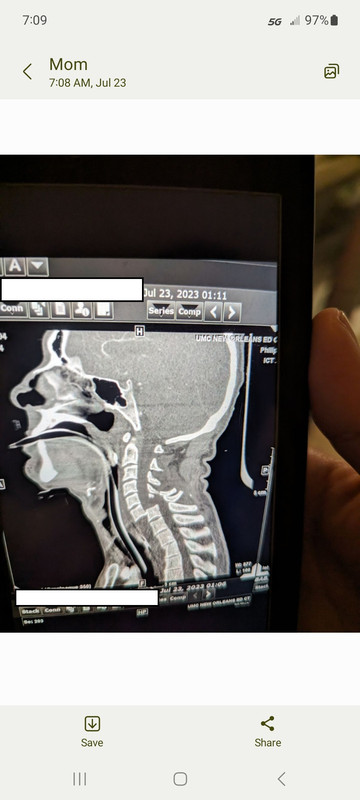

This is a horrific injury. Bilateral facet dislocations and 100% displacement of C6 on C7 with likely near complete cord injury. Honestly surprised he has any sensory function in his lowers. That CT slice screams complete cord injury. This is going to be an extremely prolonged recovery and likely never complete recovery.

I’m no expert but from that film that looks to be an almost “internal decapitation”. He’s lucky to be alive with a neck injury that severe.

Just looking at the film and knowing nothing else, his spinal cord is probably severed and he will likely be on a vent long term. Best of luck, I hope I’m wrong.

This is a C6/7 injury so Phrenic nerve to the diaphragm should be spared. Hopefully since it’s a lower cervical injury he has a good chance of respiratory recovery.